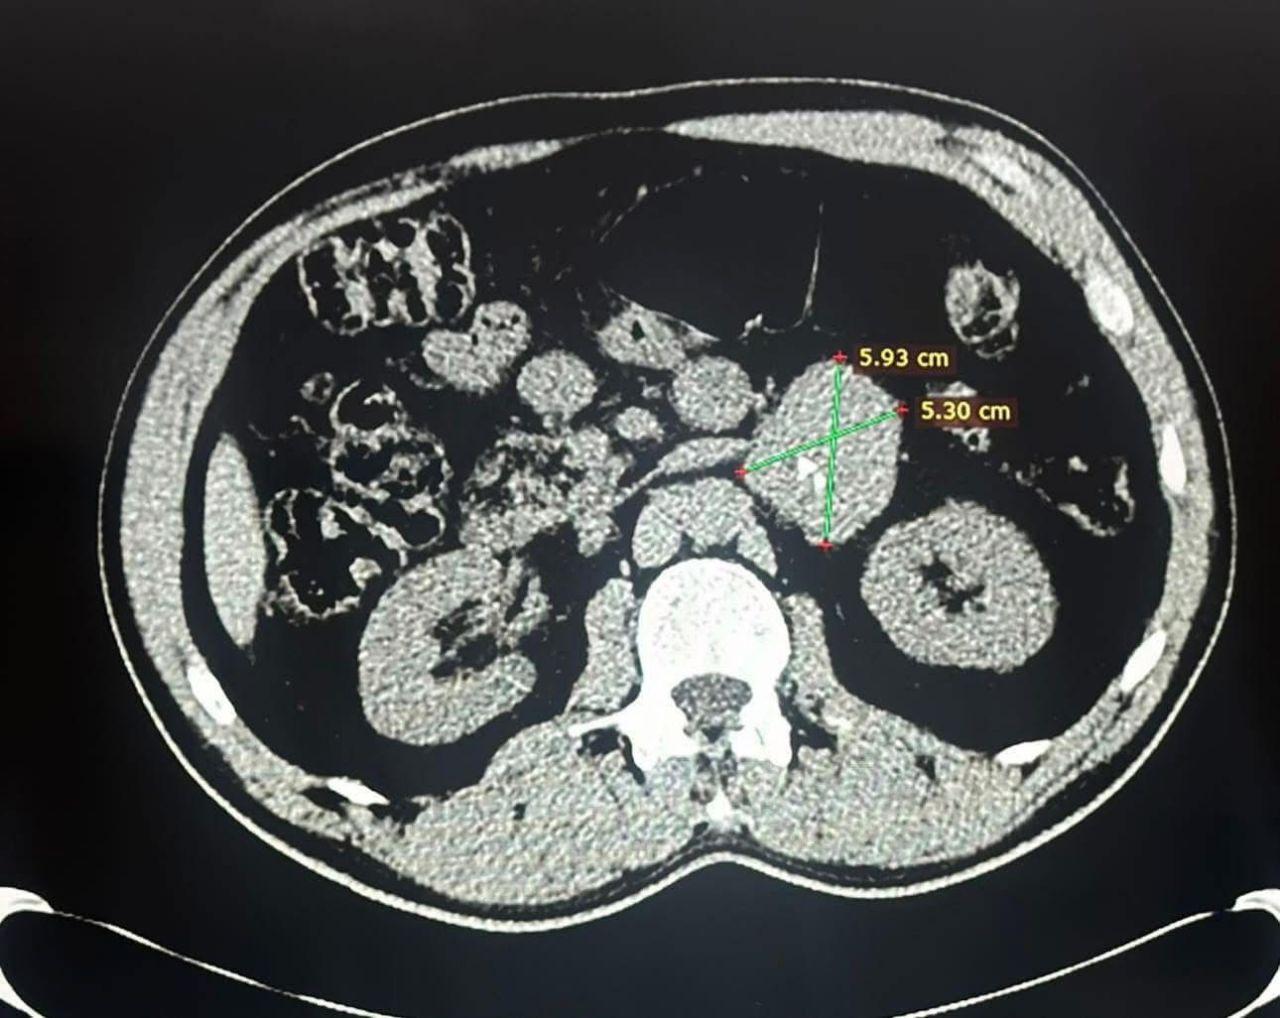

وبين عميد الكلية الدكتور نوفل علي المبارك ان العملية اجريت لمريض يبلغ من العمر(55) لاستئصال ورم الغدة الكظرية لمريض يعاني من ورم كبير الحجم ومتصل نسيجيا بالكلى اليسرى وشريانها الرئيسي.

مضيفا ان العملية تكللت بالنجاح وتم خلالها رفع الغدة الكظرية اليسرى مع الورم والكلى اليسرى.